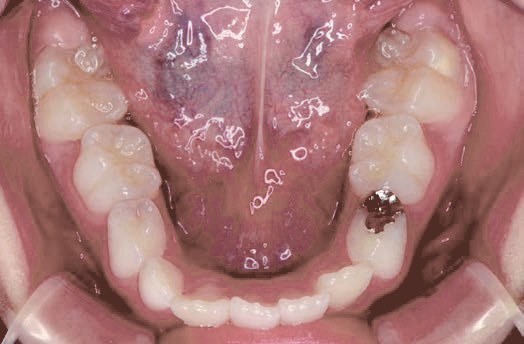

下の奥歯が内側に傾いて、舌の位置が悪く、鼻がつまって口呼吸の状態でした。扁桃腺がよく腫れ、風邪をひきやすく、いびきもあるようでした。

装置で上あごを拡大し、下の歯の位置を整え、前歯の並びを整えました。お口のトレーニングの効果で鼻詰まりと、いびきも改善。たった1年でこの変化が見られました。もちろん歯は1本も抜いていません。